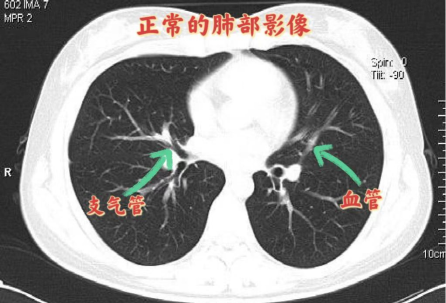

这是正常肺部的CT图像。

正常情况下肺组织是由肺泡组成的,肺泡里边充满了空气,进行CT检查时,射线穿过肺泡,整体来看影像表现应该是黑色的。

但如果肺部有感染、有炎症和渗出液的时候,肺泡就被这些渗出液或者炎性细胞所填充,在影像学上表现为白色;当炎症比较重、渗出比较多的时候,白色影像区域面积大概超过70%,在临床上大家口语化称为“白肺”。此时的肺失去了正常的生理功能,影响正常的通气、换气,在临床上表现为低氧血症、呼吸窘迫等症状。不止新冠病毒感染,细菌、支原体等严重的感染,也会出现“白肺”。